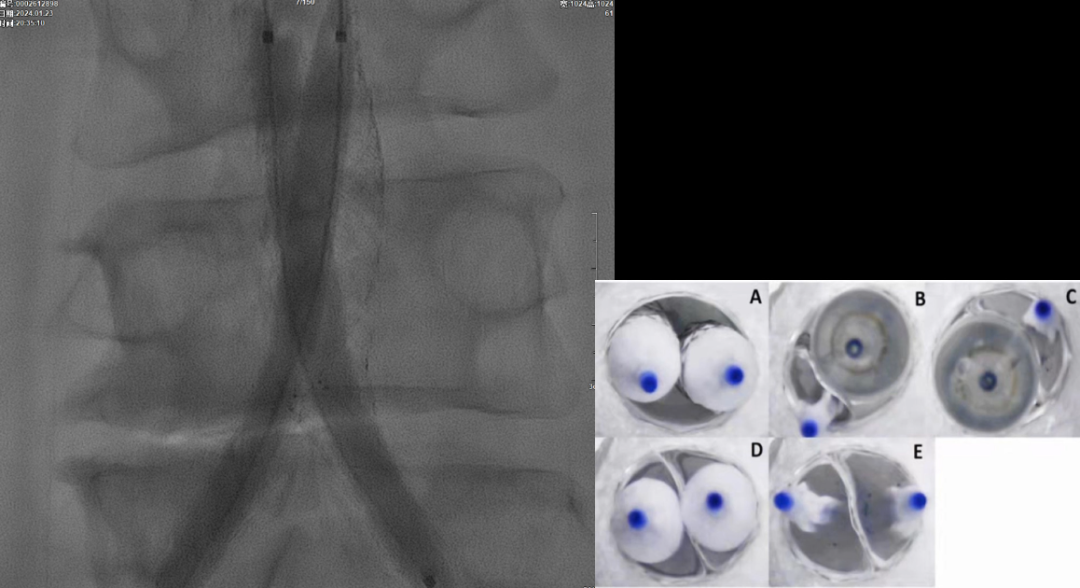

在超声引导下,成功完成双侧股总动脉穿刺。通过导管配合超滑导丝,顺利通过病变区域进入腹主动脉下段,造影明确腹主动脉下段及双侧髂动脉完全闭塞的病变范围与程度。

采用8F Rotarex导管对双侧髂动脉及腹主动脉下段进行减容处理。该器械对于陈旧性血栓具有良好的清除效果,且适用于支架内病变的治疗。减容治疗的主要目的在于获得理想的管腔空间,同时降低远端动脉栓塞的风险。

该图解释为何远端距离双侧髂总动脉分叉至少1.5cm,以避免后扩张时大球囊对髂动脉造成损伤。

CERAB技术的关键点一:经双侧股总动脉植入2枚VBX球囊扩张式覆膜支架(8L×79mm),与腹主动脉覆膜支架腔内平行放置,且两枚支架端平齐对接。